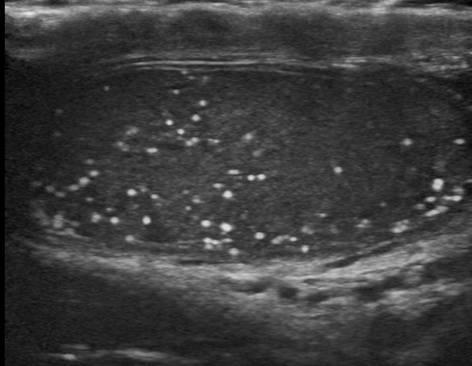

Testiular Pearls

testicular calcification

40% have neoplasm asscoiation

Microlithiasis